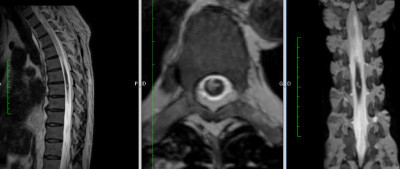

Resonancia Magnética de Columna

Envíado por Dr. José Rafael Chang Calero